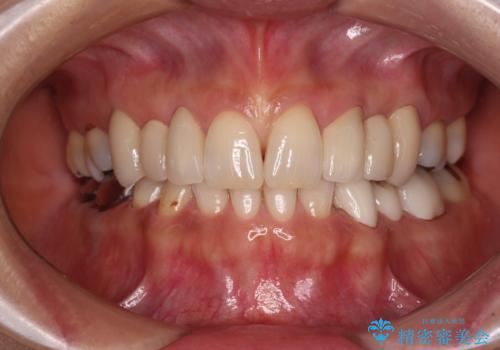

口が閉じられない ワイヤー装置による矯正治療

- 前歯が突出しているために口が閉じられないとのことで来院された患者様です。

上下ともに顎が小さく、歯列が前方に突き出していたため、上下左右の第一小臼歯4本を抜歯し、口元の突出感を改善していくこととしました。

口元の突出感が改善されると睡眠中の口呼吸が予防でき、鼻炎などの疾患予防に繋がると言われています。